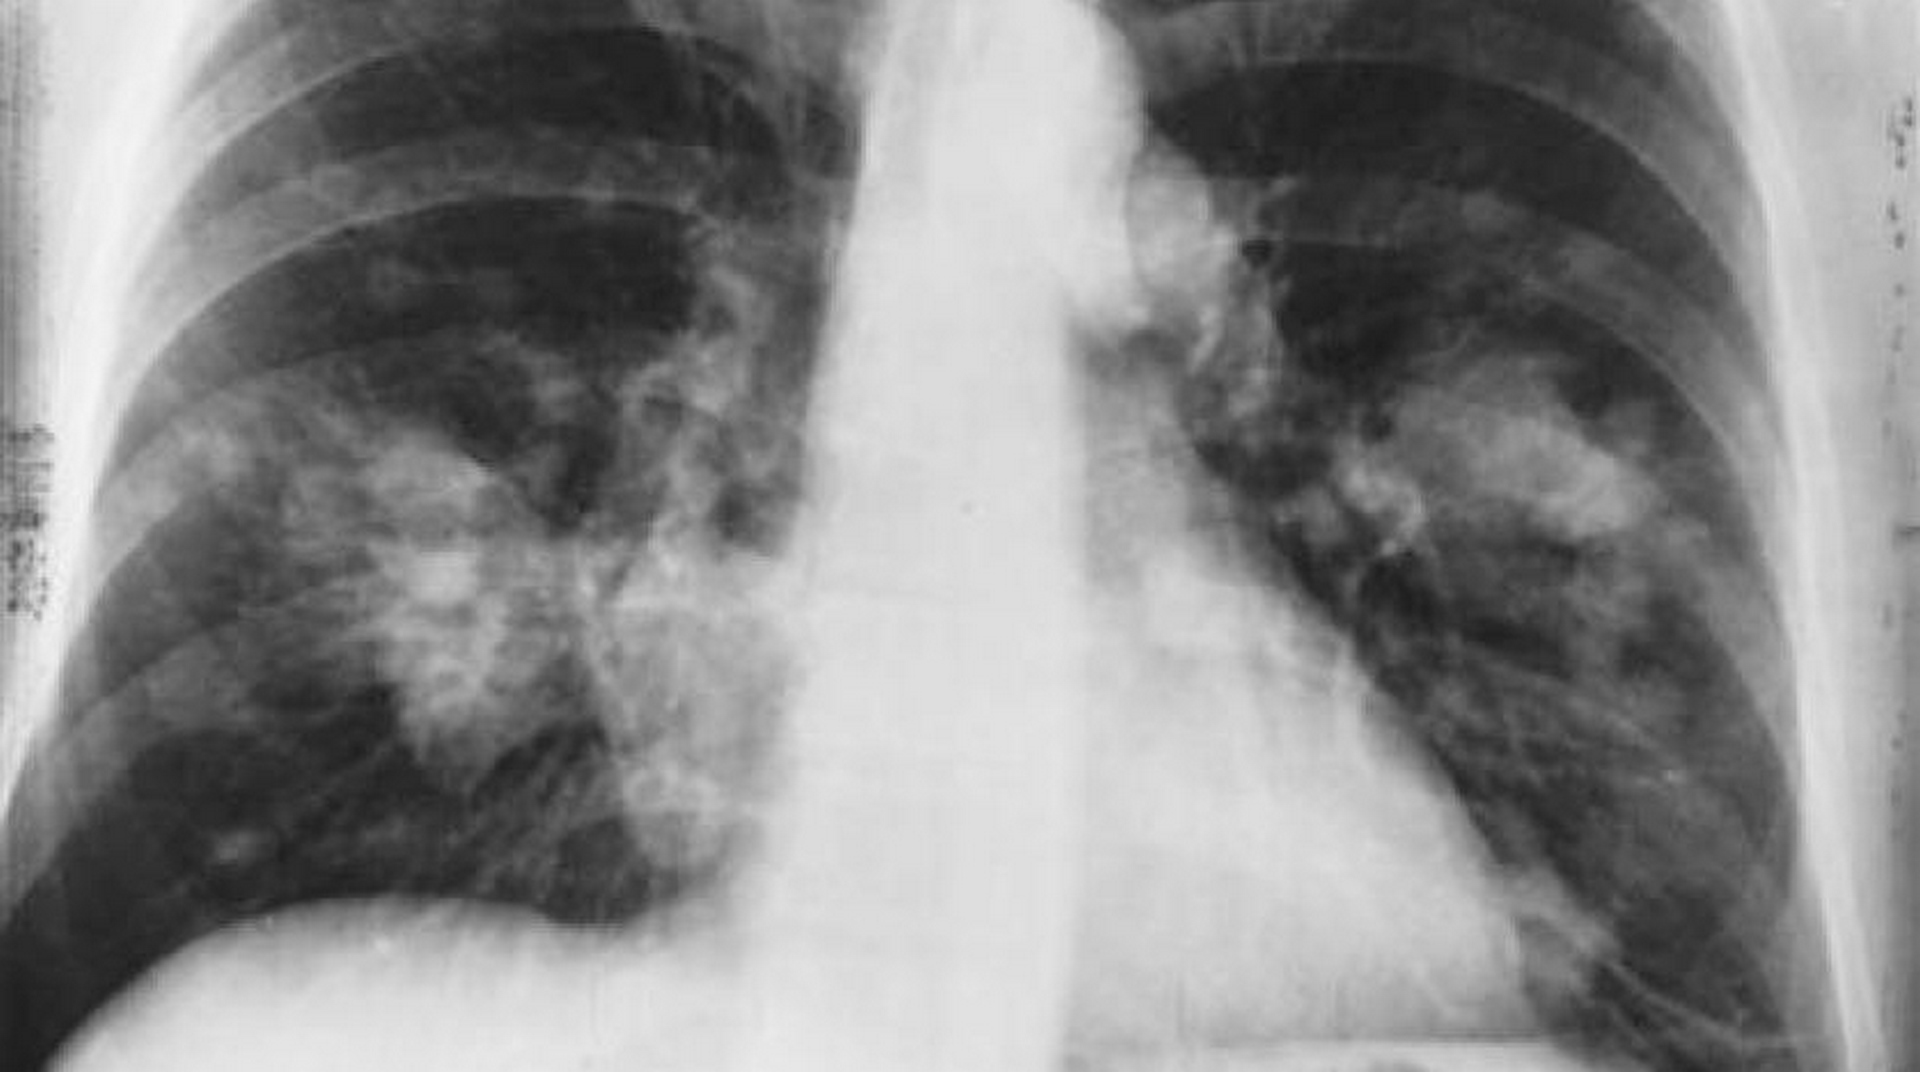

ابتكار أداة ذكاء صناعي يمكنها رصد السرطان بدقة

قام مجموعة من الخبراء بتطوير أداة ذكاء صناعي يمكنها رصد السرطان بدقة، في تطور يقولون إنه يمكن أن يسرِّع من تشخيص المرض وعلاجه.

ووفقاً لصحيفة «الغارديان» البريطانية، يمكن لأداة الذكاء الصناعي، التي صمَّمها خبراء في صندوق «مؤسسة رويال مارسدن»، و«معهد أبحاث السرطان» في لندن و«إمبريال كوليدج لندن»، تحديد ما إذا كانت الأورام غير الطبيعية الموجودة في الأشعة المقطعية سرطانية أم لا.

واستخدم الفريق الأشعة المقطعية لنحو 500 مريض يعانون من أورام سرطانية في الرئة؛ لتطوير خوارزمية ذكاء صناعي يمكنها رصد المرض بسرعة ودقة.

وأظهرت النتائج، التي نُشرت في مجلة «eBioMedicine»، أن نموذج الذكاء الصناعي المبتكَر يمكنه تحديد مخاطر الإصابة بالسرطان بدقة قدرها 0.87 على مقياس «المنطقة الواقعة تحت المنحنى»، في حين أن طرق الكشف التقليدية تتخطى دقة 0.67 على المقياس نفسه.